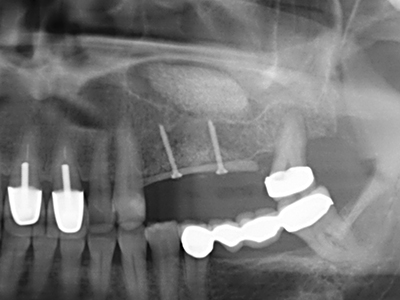

Fig. 17: Tomografía computarizada de un osteoma de crecimiento progresivo ...

Fig. 17b: justo al lado del canal alveolar con irritación nerviosa (vista lateral y coronal).